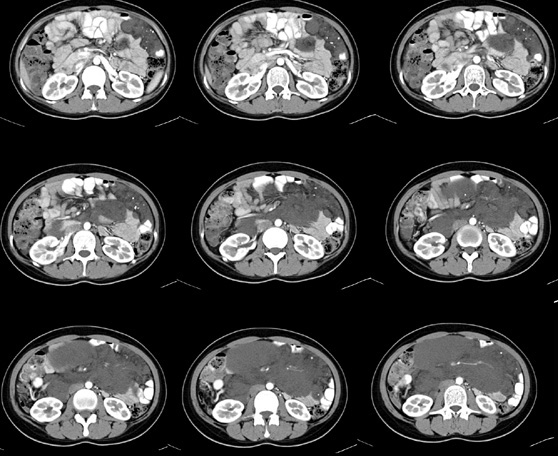

女性,28岁,停经3月,腹部膨隆1月,产前检查发现腹部占位

{肿块中心ct值27hu,增强后,动脉期、门脉期均无明显强化)

患者手术病理:腹腔囊性淋巴管瘤,象这样充满整个腹腔的的确很少见